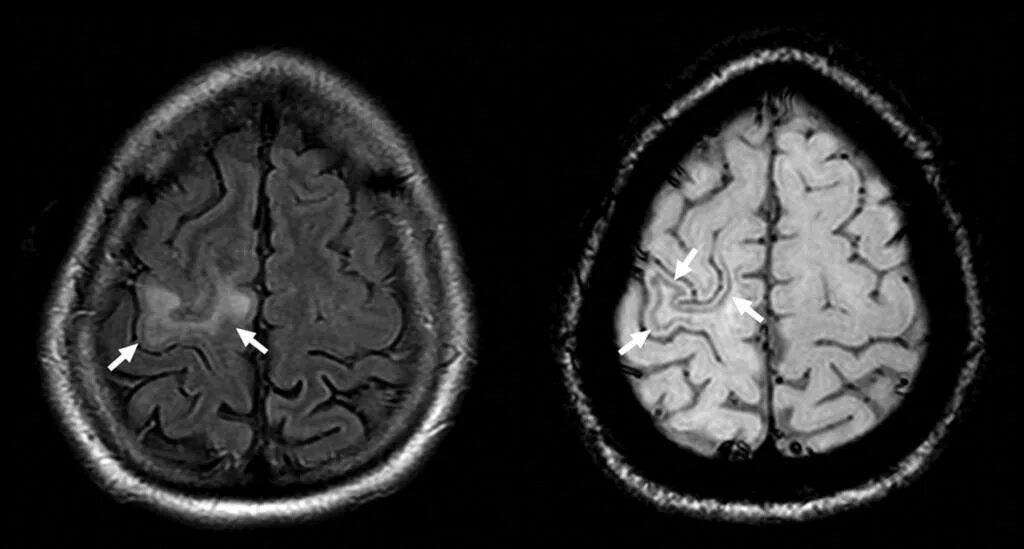

После мрт головного мозга